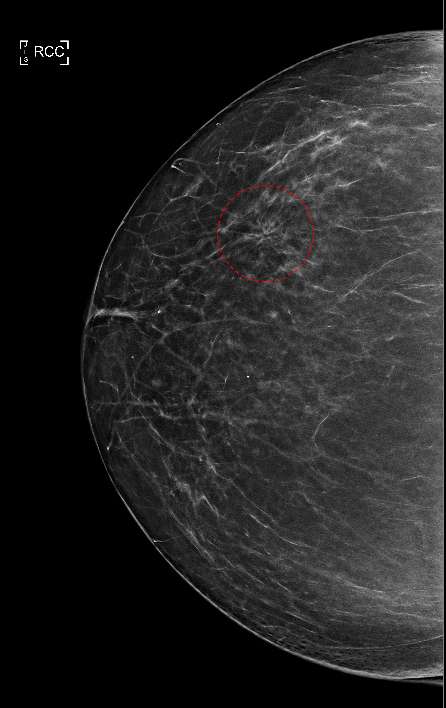

Figure 1 shows a classic mammogram appearance of architectural distortion. As denoted by the red circle, abnormal, fine tissue lines can be seen emanating in a radial pattern and appear to originate from a central focal region. This is in contrast to the surrounding normal parenchymal breast tissue which does not follow this irregular radial pattern. Architectural distortions may be present with no additional mammogram findings (as seen in Figure 1) or in association with other findings such as calcifications or dense masses.